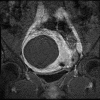

Focused ultrasound surgery (FUS) is a noninvasive image-guided therapy and an alternative to surgical interventions. It presents an opportunity to revolutionize cancer therapy and to affect or change drug delivery of therapeutic agents in new focally targeted ways. In this article the background, principles, technical devices, and clinical cancer applications of image-guided FUS are reviewed.